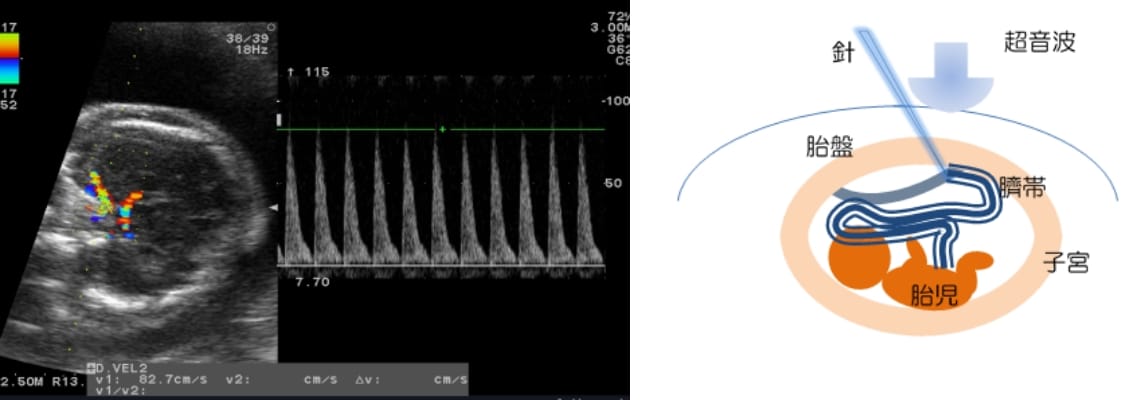

おなかの中の赤ちゃんも、さまざまな原因によって貧血になることがあります。大人の場合、血液検査によって貧血があるかどうか調べますが、おなかのなかの赤ちゃんも基本的には同じ血液検査で調べます。超音波で確認しながら、お母さんのおなかを通して針を刺し、臍帯から血液をとります。これは簡単なことではありません。そのため最近では、治療を必要とする貧血があるかどうかを、超音波検査で推測する方法が知られています。赤ちゃんの頭の中大脳動脈という部分の血流速度を測る方法です。超音波検査で胎児貧血が疑われた場合、臍帯穿刺を行い、臍帯血の採血をして確認します。

超音波で臍帯静脈の位置を確認しながら、採血に使う細い針を用いて、臍帯静脈を穿刺し、輸血を行います。貧血の原因によっては、何度か輸血を繰り返すこともあります。